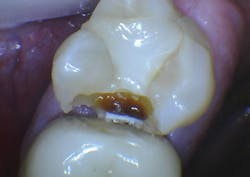

Upon initial examination of the radiograph, only a few minor lesions were observed. When the dentist excavated the caries in the maxillary second molar, the extreme depth of the lesion was able to be seen. This is not an abnormal finding. In spite of the ability to manipulate digital images through magnification, coloring, texturing, and change of contrast, most small lesions and some large lesions are often missed.

Figure 2: On making the initial opening of the mesial surface of the second maxillary molar, the extreme depth of the lesion is evident.